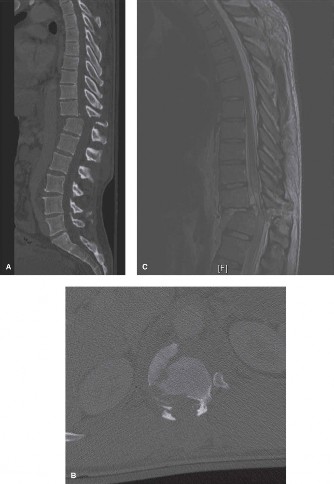

The diagnostic imaging workup for this patient spanned his initial presentation at age 15 and his subsequent return at age 20, providing a textbook illustration of the natural history of untreated isthmic spondylolysis. During his initial visit, standard weight-bearing anteroposterior (AP), lateral, and bilateral oblique radiographs of the lumbar spine were obtained. The lateral radiograph demonstrated a normal lumbar lordosis and preserved L5-S1 disc space height, with no evidence of anterior translation (spondylolisthesis). However, the oblique radiographs revealed the pathognomonic "collar on the Scotty dog" sign. The "Scotty dog" represents the posterior elements of the vertebra, where the nose is the transverse process, the eye is the pedicle, the front leg is the inferior articular process, and the neck is the pars interarticularis. A radiolucent line across the neck confirmed the presence of bilateral L5 pars defects.

Had the patient been compliant with follow-up during his initial presentation, advanced imaging such as a Single Photon Emission Computed Tomography (SPECT) scan or a Magnetic Resonance Imaging (MRI) scan with Short Tau Inversion Recovery (STIR) sequences would have been indicated. These modalities are highly sensitive for detecting acute stress reactions and marrow edema in the pars interarticularis before a frank fracture line becomes visible on plain radiographs. An MRI at that early stage would have likely shown high signal intensity in the bilateral L5 pars regions on T2-weighted STIR images, confirming an active, metabolically "hot" lesion that possessed a high potential for healing with rigid bracing.

Upon his return five years later, the imaging profile was drastically different. Standing lateral radiographs now revealed a Meyerding Grade 2 spondylolisthesis at L5-S1, indicating that the L5 vertebral body had translated anteriorly by 25% to 50% over the sacral promontory. Furthermore, there was a noticeable collapse of the L5-S1 intervertebral disc space, signifying advanced degenerative changes secondary to the altered biomechanics and chronic instability. We also meticulously measured the patient's spinopelvic parameters on a standing 36-inch scoliosis cassette. His Pelvic Incidence (PI) was measured at 65 degrees (high), which mathematically dictates a higher Sacral Slope (SS) and Pelvic Tilt (PT). A high PI is a known biomechanical risk factor for the progression of spondylolisthesis, as it creates a steeper lumbosacral shear angle, placing immense anterior translational force across the compromised L5-S1 segment.

To evaluate the neural elements and the soft tissue structures, a comprehensive MRI of the lumbar spine without contrast was obtained. The T2-weighted sagittal and axial sequences confirmed the Grade 2 anterolisthesis and demonstrated severe bilateral foraminal stenosis at L5-S1. The exiting L5 nerve roots were severely compressed between the hypertrophied, fibrocartilaginous pseudarthrosis tissue of the pars defect dorsally, and the bulging, degenerated L5-S1 disc and superior endplate of S1 ventrally. Furthermore, the MRI revealed Modic Type II changes (fatty replacement of the subchondral bone marrow) in the adjacent vertebral endplates, confirming chronic biomechanical stress and discogenic degeneration. The central canal remained relatively patent, which is characteristic of isthmic spondylolisthesis, as the posterior neural arch is left behind during the anterior translation of the vertebral body.